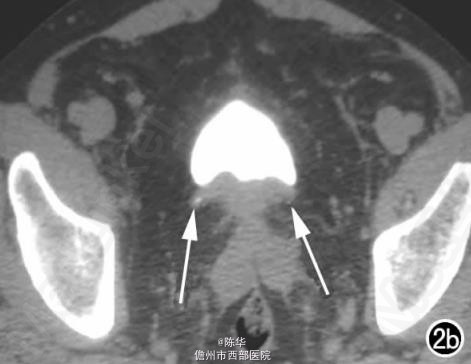

腹部B超示双肾增大,双肾慢性肾病声像;双肾中度积液伴双输尿管上段扩张。 IVPshi双侧输尿管中或下段梗阻。 膀胱造影:经尿道置管后,注射对比剂充盈膀胱,膀胱下半部先充盈,继续灌注对比剂后见膀胱完全显影,膀胱形态异常,呈“倒葫芦状”(图1)。 CT增强扫描行延迟期 MPR重组,见双侧肾盂、肾盏扩张积液;双侧输尿管纡曲、扩张,下端呈鸟嘴样变窄;膀胱变形、体积减小(图2); MRI平扫示双侧肾盂、肾盏扩张积液,双侧输尿管扩张并下端鸟嘴样变窄,盆腔内多量脂肪沉积,分布于膀胱、直肠周围,T1WI、T2WI呈明显高信号,T2WI抑脂像呈稍高信号,膀胱受压变形、体积减小(图3a~c); MRU示双侧肾盂肾盏扩张、积液,双侧输尿管显著纡曲、扩张,下端鸟嘴样变窄,管壁光整,膀胱变形、体积较小、位置抬高(图3d)。